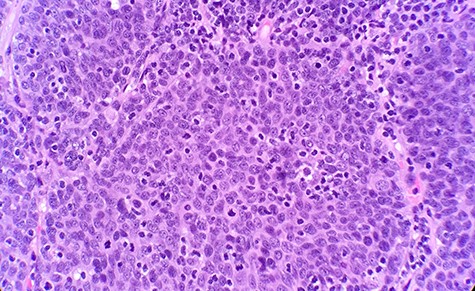

The patient had a past medical history of hypertension, diabetes mellitus type 2 and hyperlipidemia. Three years before this, the patient was diagnosed with left lung small cell carcinoma on cytology and underwent chemotherapy with surveillance screening. The patient presented for a left lung biopsy and left subclavian mediport placement following the detection of a lingular nodule. Grossly, the lingular nodule specimen measured 3.3 × 3.0 × 1.4 cm, and cut sections showed a tan mass measuring 1.5 × 2 cm. Microscopic examination revealed that the tumor was comprised of nests of small blue cells with high nuclear/cytoplasmic (N/C) ratio and high mitotic activity (Fig. 1). No morphological features of squamous differentiation were seen. Tumor cells have distinct nucleoli and no molding make small cell carcinoma less likely. IHC stains reveal that tumor cells were positive for squamous cell markers (p40, p63 and CK5/6) (Fig. 2), Pan Keratin, TTF1 (focal) and negative for neuroendocrine markers (CD56, chromogranin and synaptophysin) (Fig. 3) and CD45. Ki 67 immunostain has ~70% positivity. Combined with morphological features, this immunochemical profile supported a diagnosis of the poorly differentiated non-keratinizing squamous cell carcinoma rather than small cell carcinoma.

Microscopic examination reveals nest of small blue cells with high N/C ratio (HE ×40).